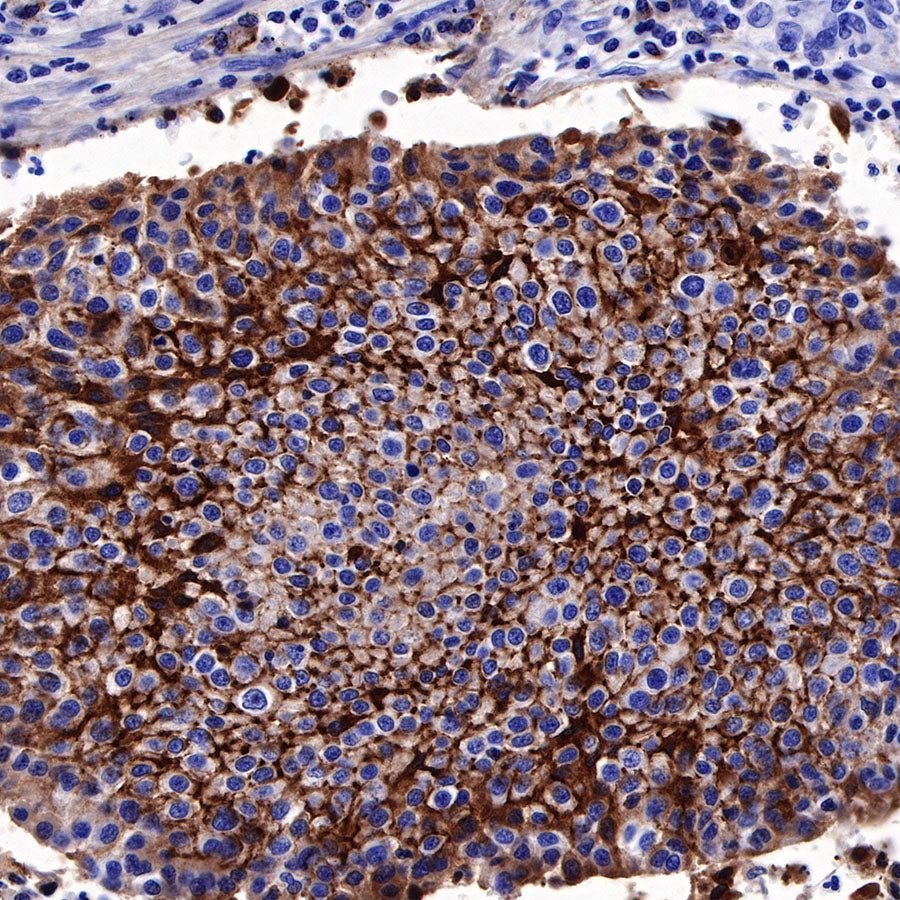

Immunohistochemistry